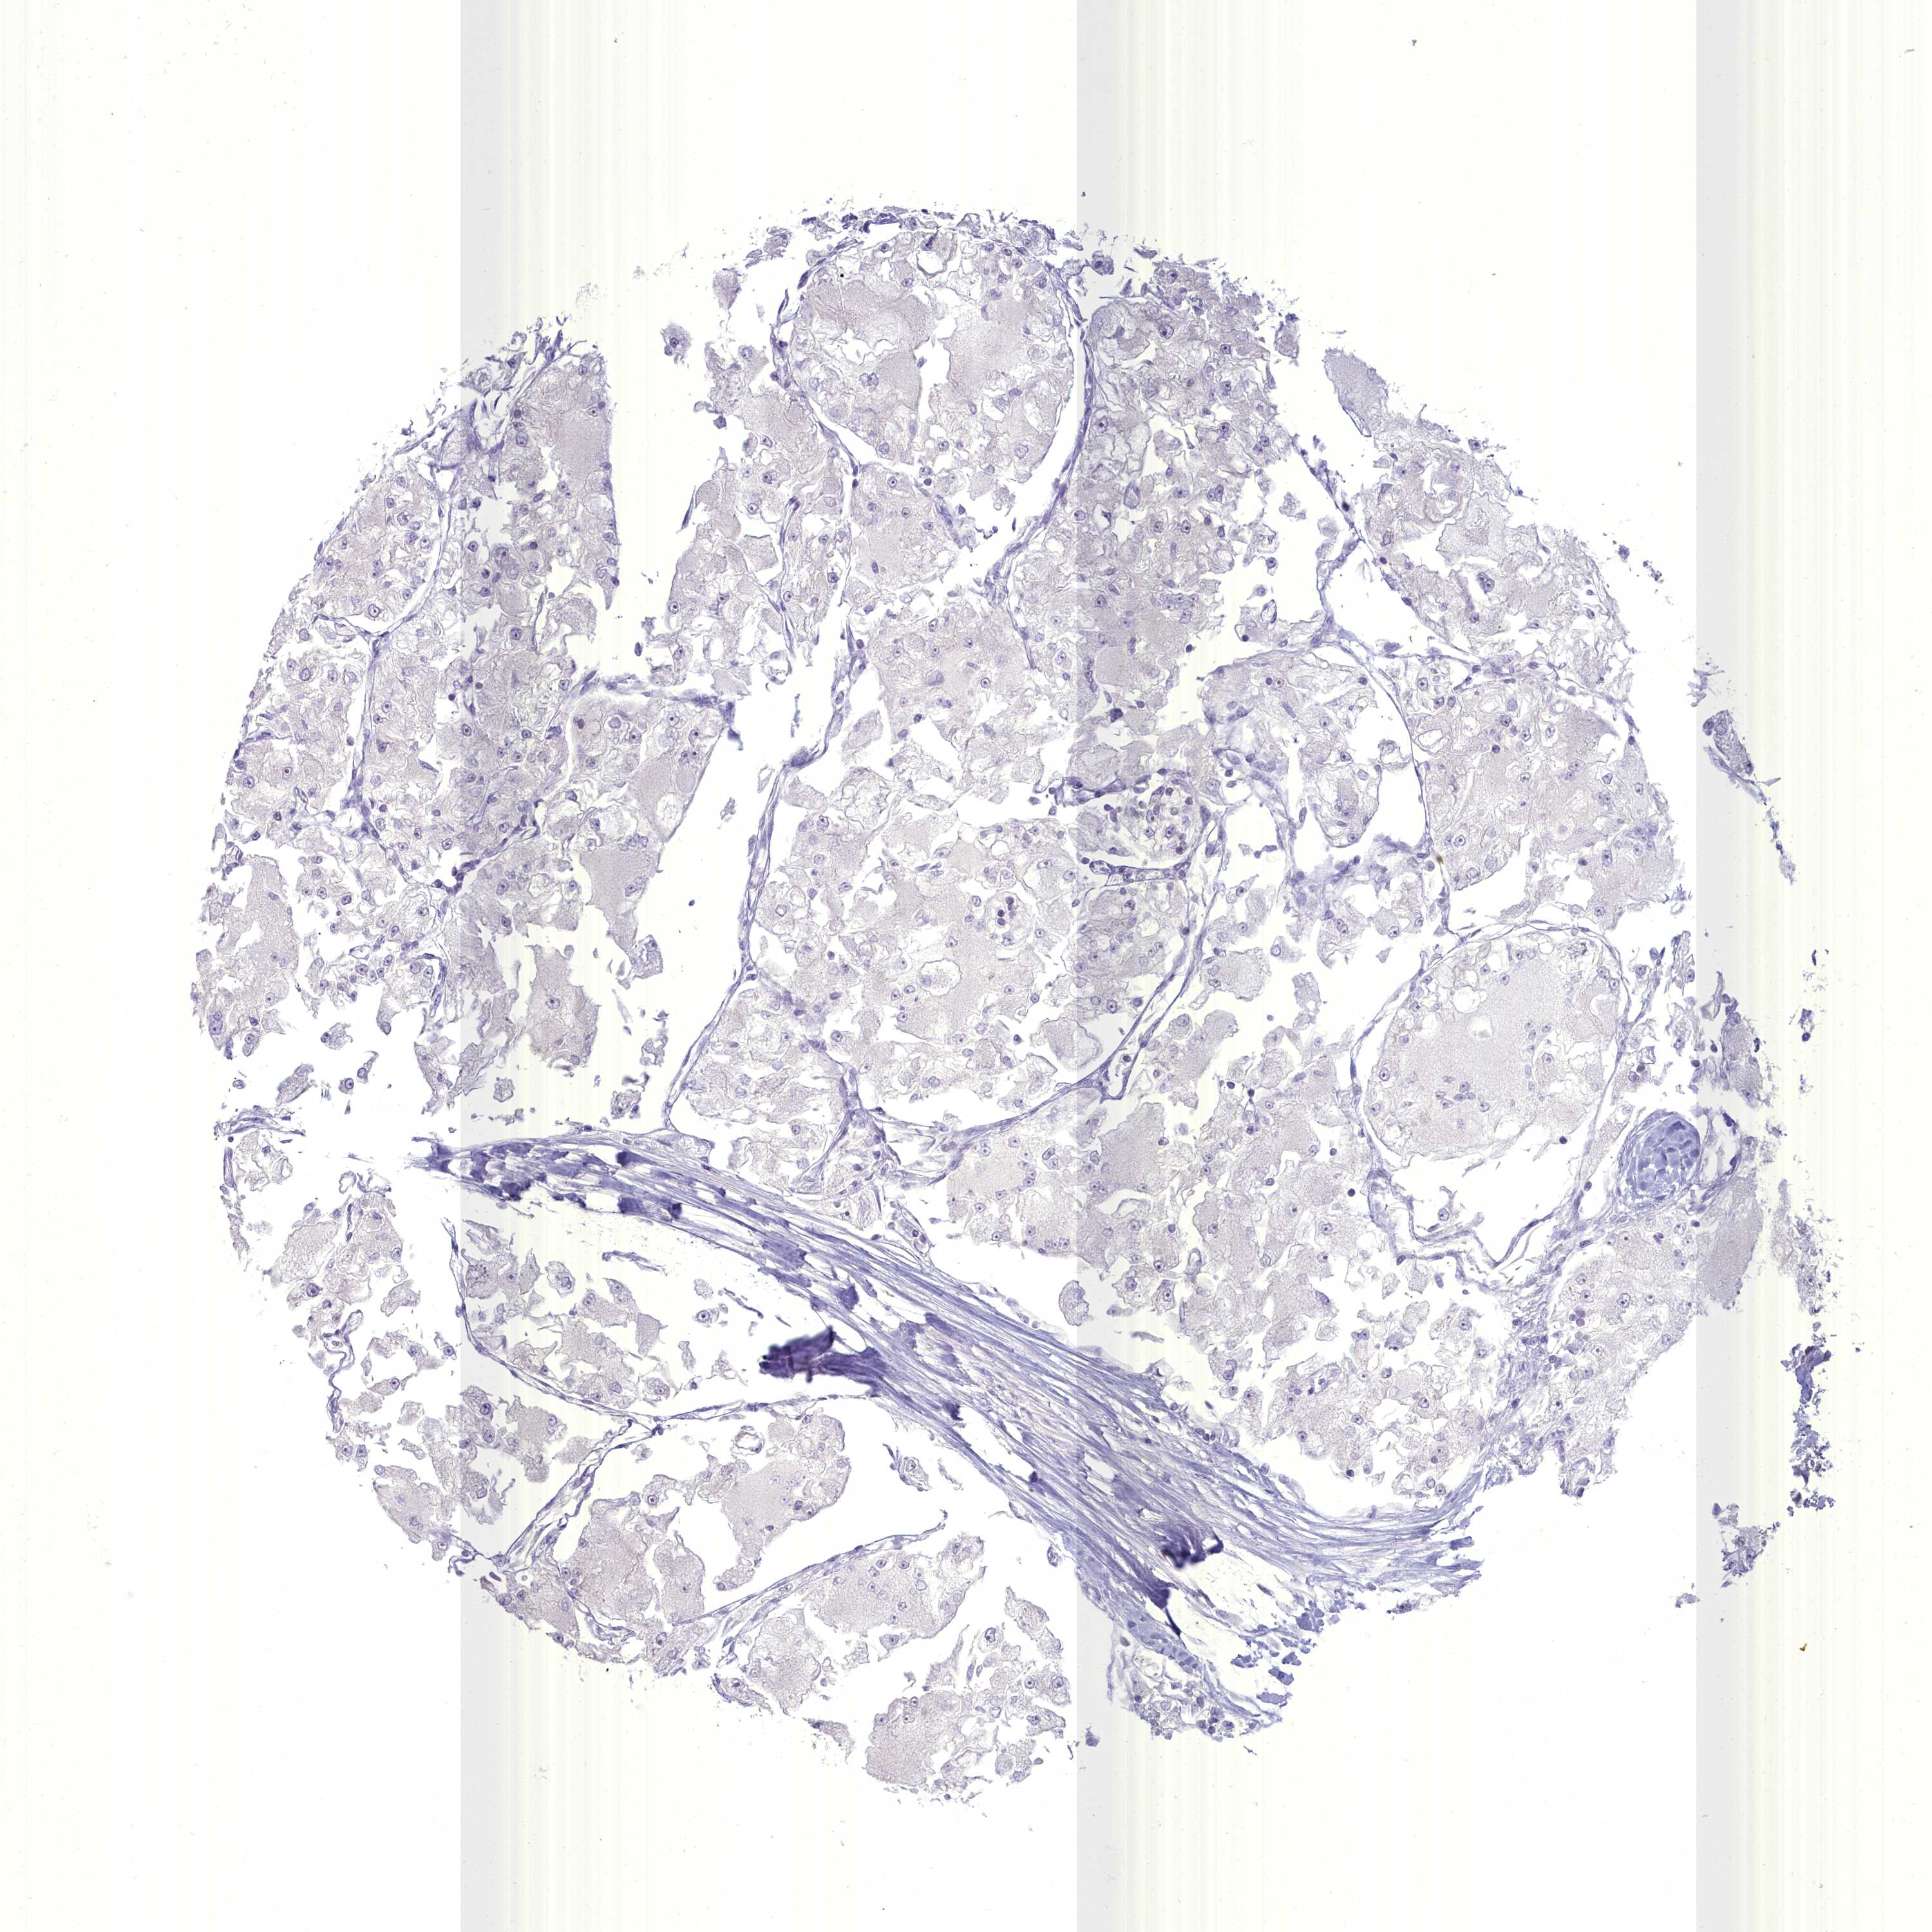

CANCER RENAL CANCER Show tissue menu

KICH TCGA KIRC TCGA KIRC VALIDATION KIRP TCGA PROTEIN RCC CPTAC PROTEIN EXPRESSION